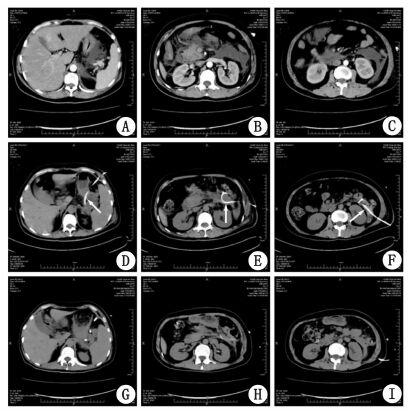

早期联合CT及B超引导下行腹腔引流(双腔ARROW管)及胰周(图 1)各腔隙引流(包括胰周、小网膜囊、两侧结肠旁沟、肠系膜根部后方等), 部分患者因重要器官阻挡、多腔分隔以及家属拒绝等因素未能接受胰周引流。

图 1 CT及超声示胰周各腔隙积液及置管引流情况